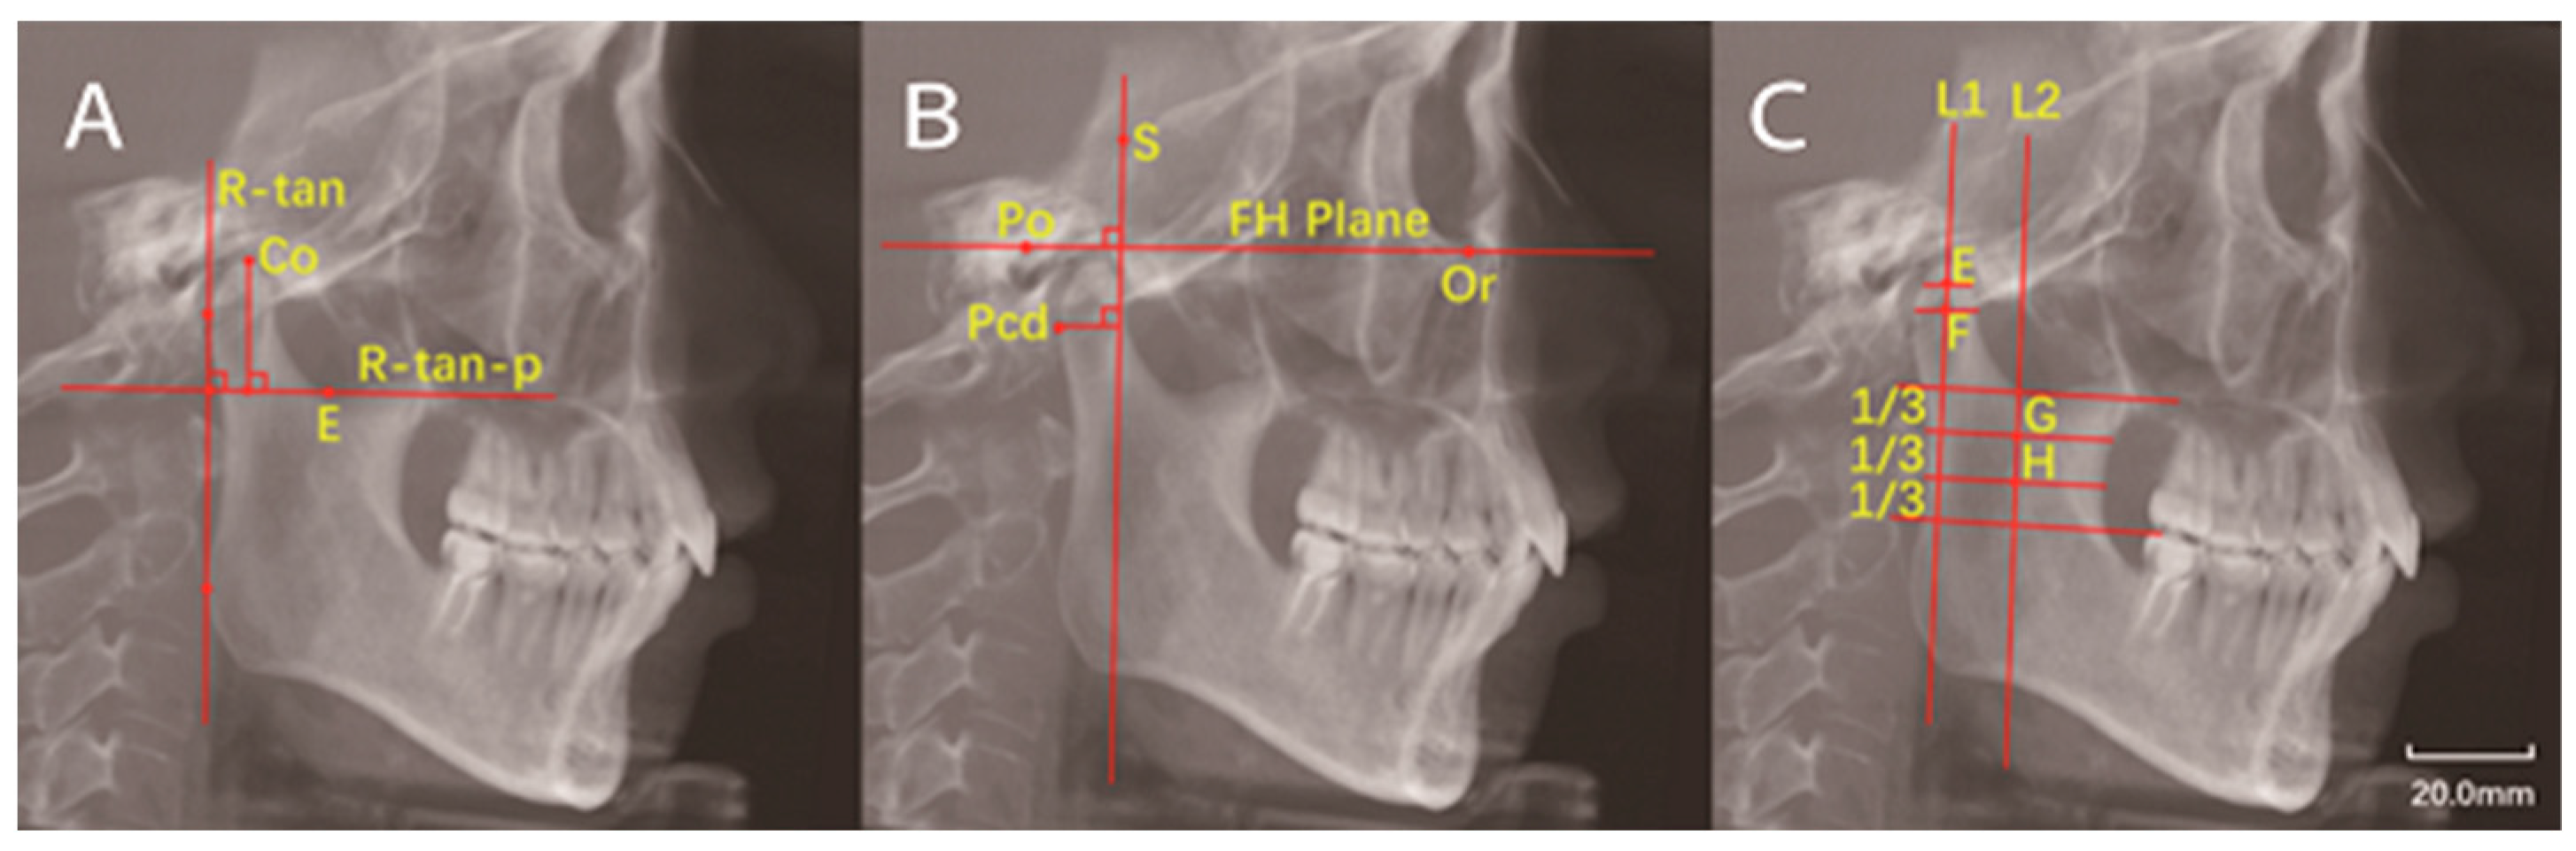

| Superior condylar point | Co | Most superior point of the condyle |

| Posterior condylar border point | Pcd | Most posterior point of the condyle on sagittal plane |

| Sella | S | The center of sella on the median sagittal plane of skull |

| Porion | Po | The uppermost point of external auditory canal |

| Orbitale | Or | The lowest point of orbital margin |

| Ramus tangent line | R-tan | Tangent to the posterior border of the ramus |

| Ramus tangent line perpendicular | R-tan-p | Line perpendicular to R-tan and tanging the deepest point of the sigmoid notch |

| Frankfort horizontal plane | FH plane | Line from Po to Or |

| Condylar height | - | Vertical distance from Co to R-tan-p |

| - | Pcd-FH-p(S) | Vertical distance from Pcd to FH-p(S) |